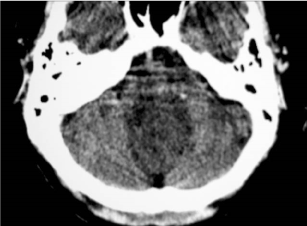

A contrast CT scan demonstrated a large well circumscribed non-enhancing hypodense midline mass lesion in the posterior fossa (Figure 1). The lesion extended from the midline to the adjacent brain parenchyma.

Figure 1. A post-contrast CT scan demonstrate a large non-enhancing hypodense mass in the posterior fossa.